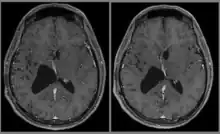

Le diagnostic est réalisé grâce à l'imagerie cérébrale, scanner ou au mieux IRM cérébrale, retrouvant cette formation hétérogène à trois composantes en général (tissulaire +/- kystique et calcique), avec rehaussement partiel à l'injection de produit de contraste.

Elle permet d'étudier les rapports avec les zones fonctionnelles du cerveau (notamment le pilier du fornix, un des composants du circuit de Papez responsable de la mémoire antérograde), le système vasculaire (réseau veineux profond), ainsi que le retentissement de la tumeur sur le cerveau (effet de masse de par l'hydrocéphalie, œdème, hémorragie, engagement…).